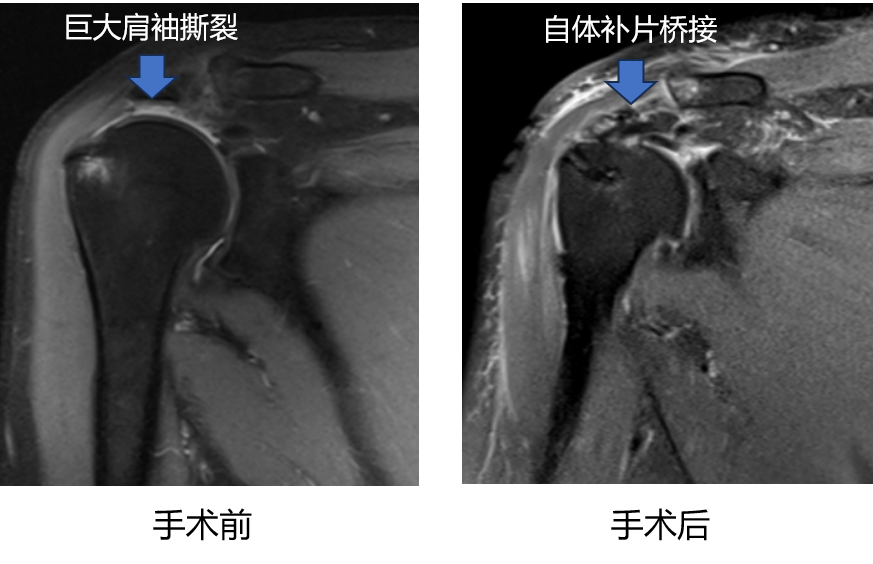

结合症状表现和相关影像资料,李欢发现王先生的肩关节里面竟然有个“大窟窿”——右肩袖部位存在巨大的撕裂,残存肩袖组织回缩明显且伴有脂肪浸润,造成关节疼痛和肌肉无力,需要通过手术进行修复。巨大肩袖撕裂是指肩袖肌腱前后方向或内外方向撕裂大于5cm或达到2个或以上的肩袖肌腱撕裂,在所有肩袖病变中占10%-40%,是肩关节最具挑战的疾病之一,好发于中老年人群以及运动员、教师、油漆工人等容易过度使用肩关节的人群。巨大肩袖撕裂的治疗是世界性难题,修复后肌腱难愈合,再撕裂率高,严重者需行肩关节置换,费用庞大,假体使用寿命有限。“由于肩袖撕裂很难通过保守治疗自我愈合,若不治疗,王先生的右手后期很可能将丧失大部分功能!”考虑常规肩袖修补手术缝合张力大,极易造成肩袖不愈合和再撕裂,经充分考虑,李欢建议开展特殊的肩袖修补方法——“补片桥接”手术。

“补片桥接”手术,就是以关节镜微创的方式,将用来修补的材料缝合到肩袖缺损部位,使其发挥桥梁支架作用,从而促进损伤部位组织快速愈合,改善关节功能。考虑人工补片材料昂贵,结合王先生的经济情况,李欢建议采取王先生大腿外侧几个平方厘米大小的阔筋膜作为补片,“就像衣服破了,如果是早期小的破口直接把边边缝合就可以了。现在破口很大,补片桥接就是取一块同样的衣料作为补丁把破口修补缝合。我们会从你大腿部位取块组织修补缝合,这样也减少了身体的免疫排斥反应。”“移花接木”的方法,让王先生倍感信心。然而这项技术步骤复杂、技术要求高,被称为肩关节镜手术技术的“天花板”,对术者来说是极大的考验。李欢带领团队做好了详细的手术方案和应急预案,团队最终分两组同时进行,一组由徐鹏带领,在大腿外侧取阔筋膜进行补片的制备,另一组由李欢、方盛进行关节镜下修复。在麻醉和护理团队的密切配合下,团队凭借精湛的技术顺利完成手术。据悉,这也是团队开展的全市首例此类手术。术后,王先生的肩关节疼痛症状明显好转,功能也得到了显著改善。